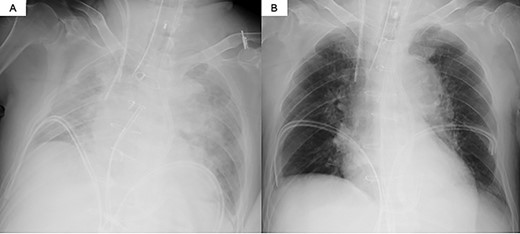

The decision was made to proceed first with PAB to stabilize the hemodynamics and delay the timing of surgical repair. After median sternotomy, PAB was attempted with a 4-mm wide Teflon felt band. The size of the band was adjusted to where the left to right shunt disappeared under transesophageal echocardiographic guidance (Fig. 1). Postoperative echocardiography revealed a bidirectional shunt through the VSR (Qp/Qs = 1.3), and the chest radiography showed decreased pulmonary congestion (Fig. 2). Cardiac output was maintained to allow adequate end-organ perfusion after PAB (urinary output >100 ml/h). Surgical VSR closure with the infarct exclusion technique and coronary artery bypass grafting were performed 7 days after PAB. The PAB was released after the initiation of cardiopulmonary bypass. Through the infarction area of the left ventricle, the right and left sides of the VSR and infarcted area were approached and covered with a bovine pericardial patch. No residual left to right shunt was observed on transesophageal echocardiography. On postoperative Day 32, the patient was discharged to a rehabilitation hospital.